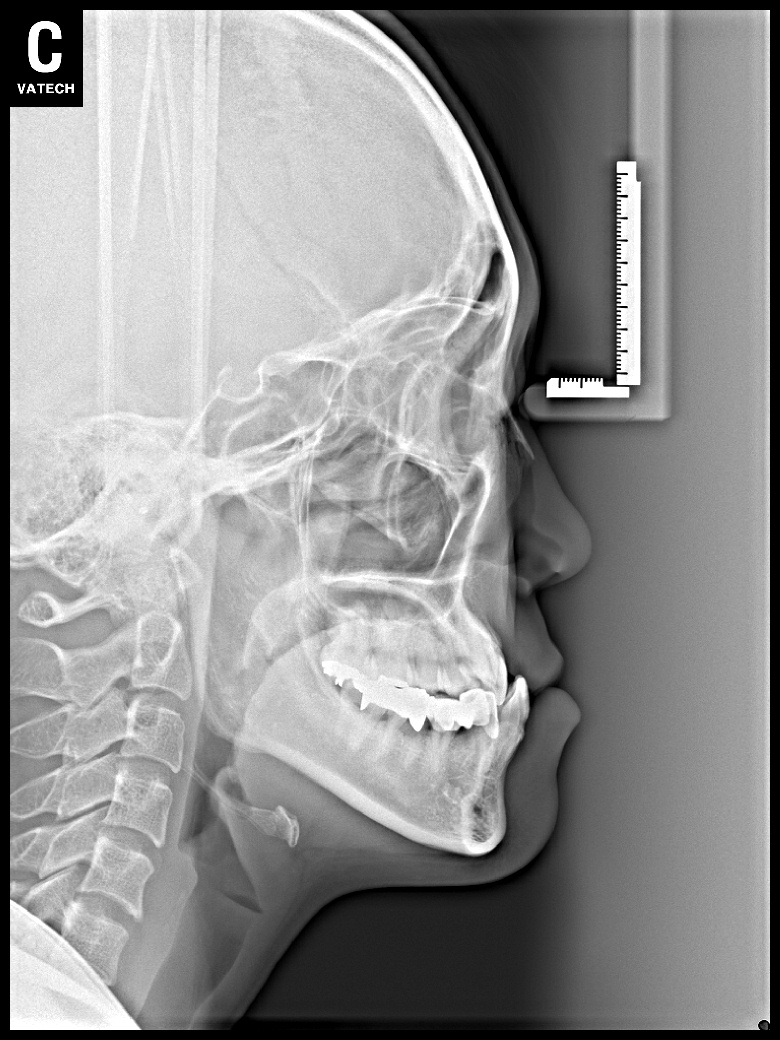

치료 후 사진입니다.